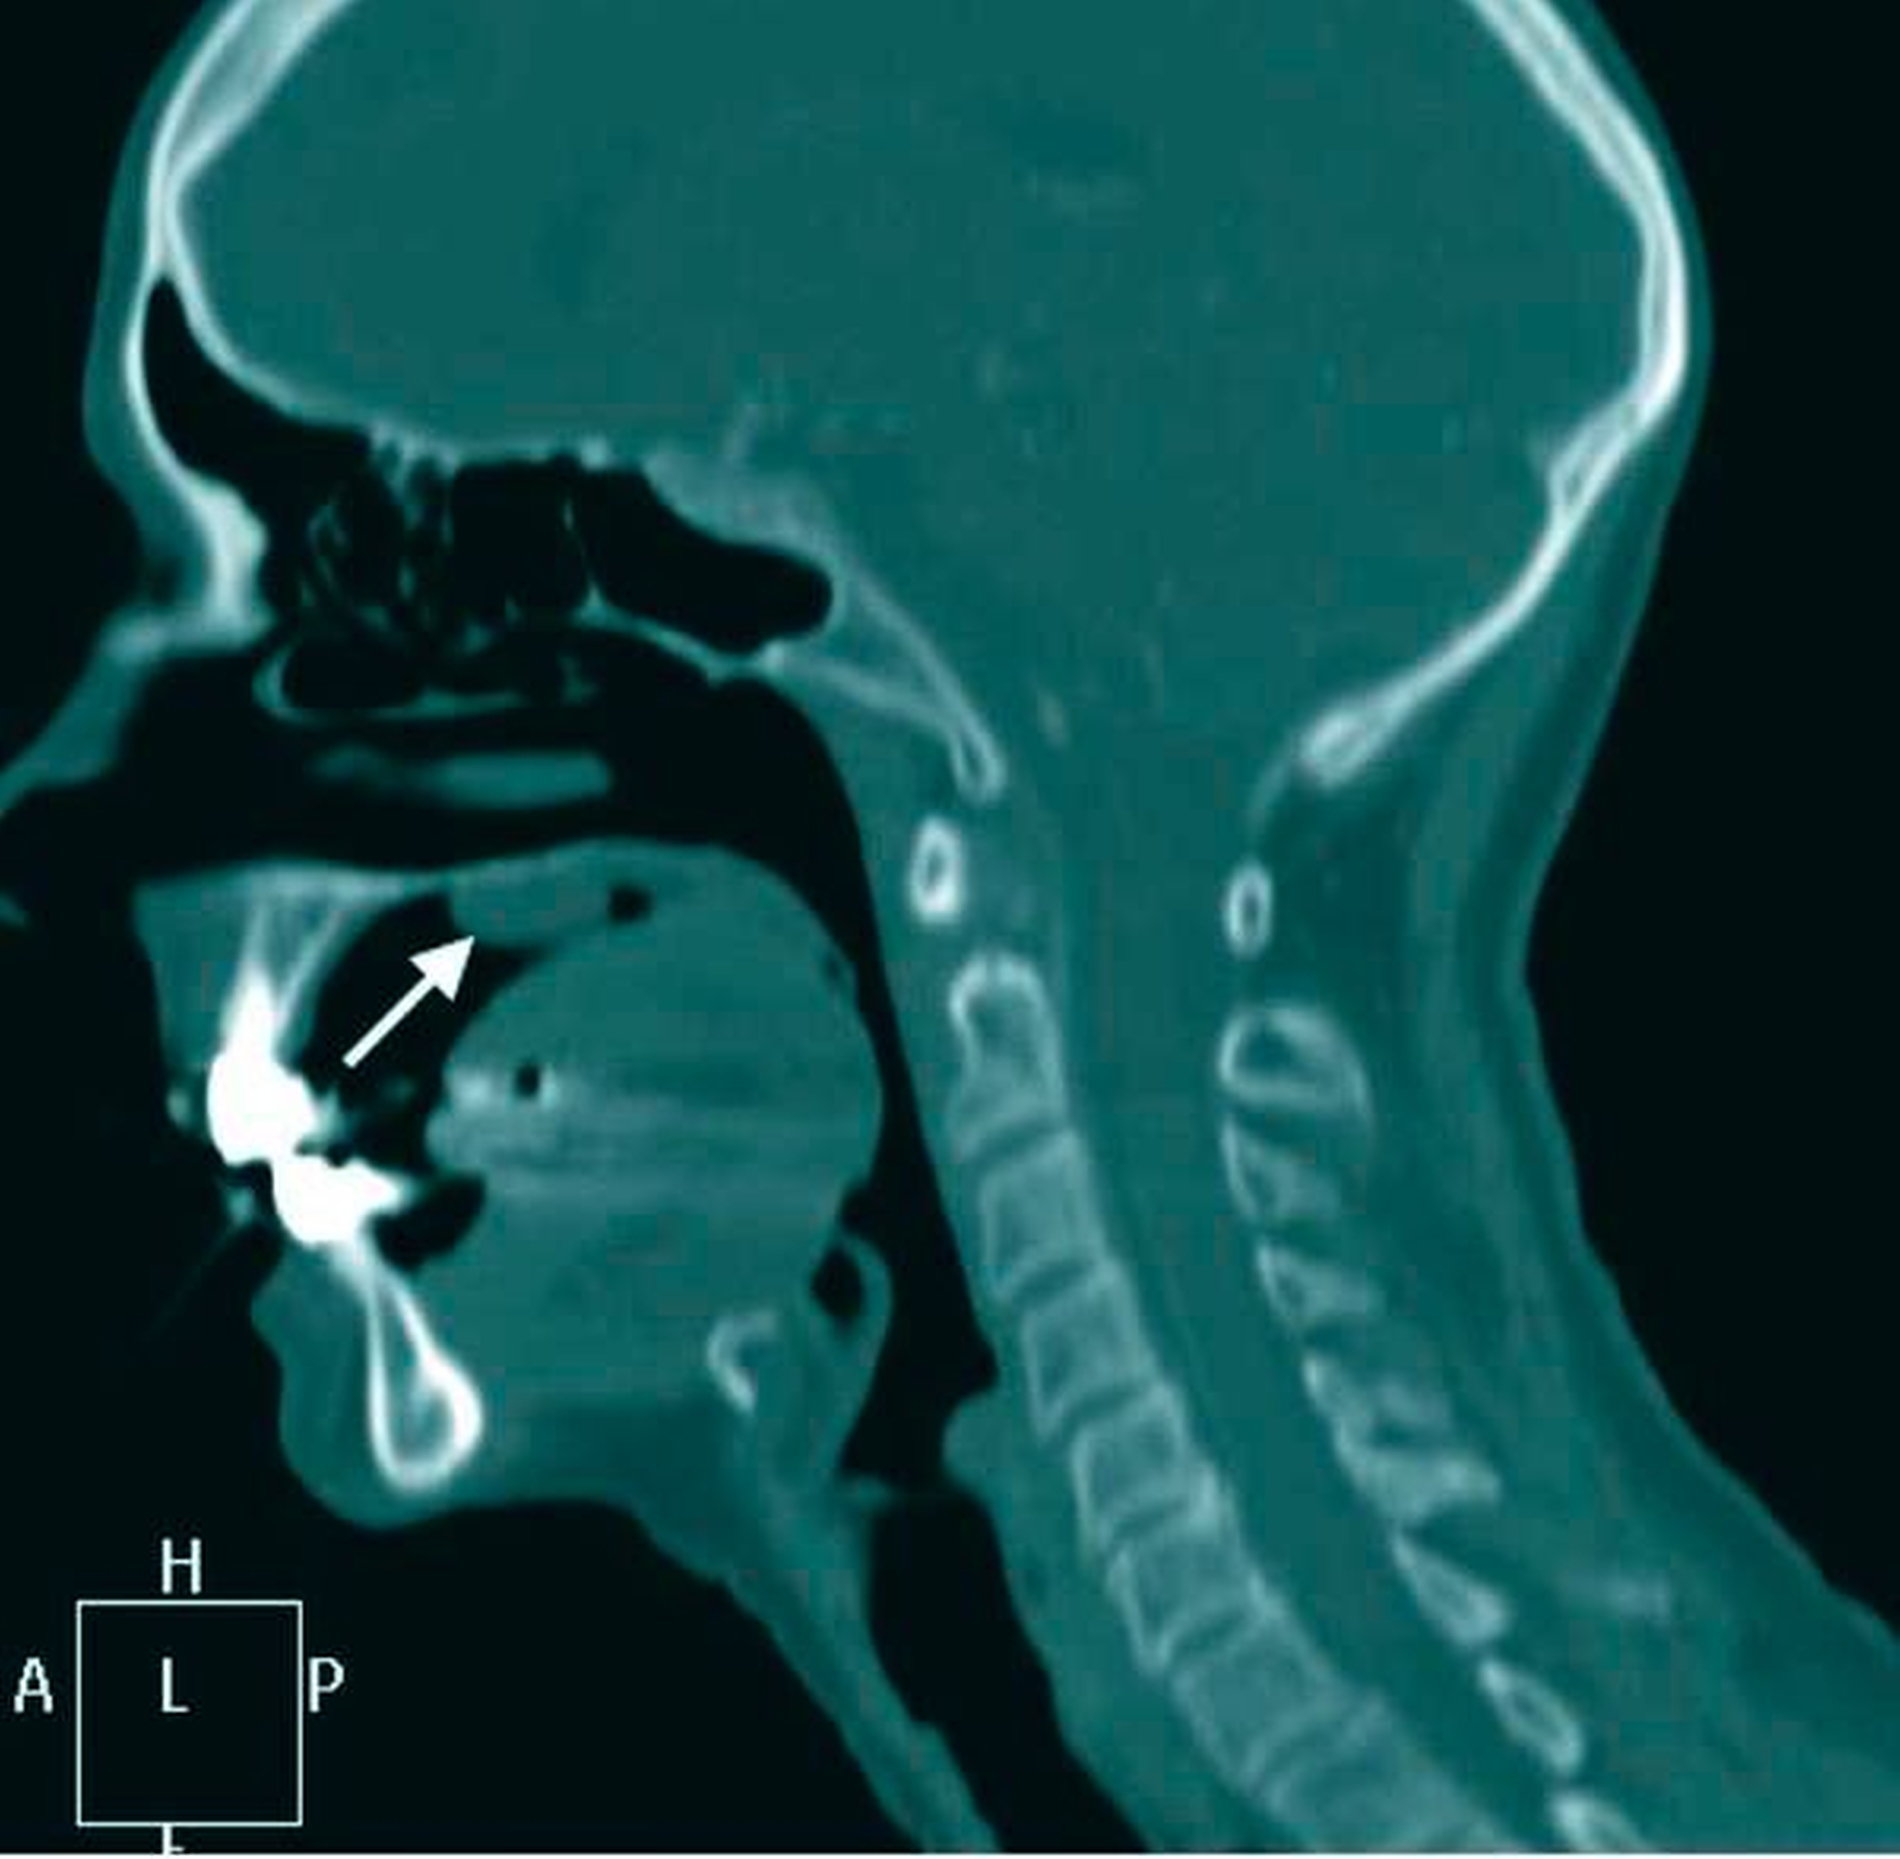

Zur Komplettierung der Diagnostik und zur Darstellung der Tiefenausdehnung des intraoralen Befunds in die angrenzenden Nachbarstrukturen erfolgte ein Kontrastmittel-gestütztes CT der Kopf-Hals-Region (Abbildungen 2a und 2b).

Weiter ist die Durchführung schnittbildgebender Verfahren (Kontrastmittel-CT oder MRT) ein wichtiges Diagnostikum, um eine Infiltration von Nachbarstrukturen auszuschließen, was wiederum das therapeutische Vorgehen beeinflusst [Kinoshita et al., 2016]. Im Fall des polypösen Mundschleimhautfibroms ist eine Spontanremission nicht zu erwarten, so dass die lokale Exzisionstherapie ohne Sicherheitsabstand mit histopathologischer Nachuntersuchung das Verfahren der Wahl darstellt [Mishra and Pandey, 2016].